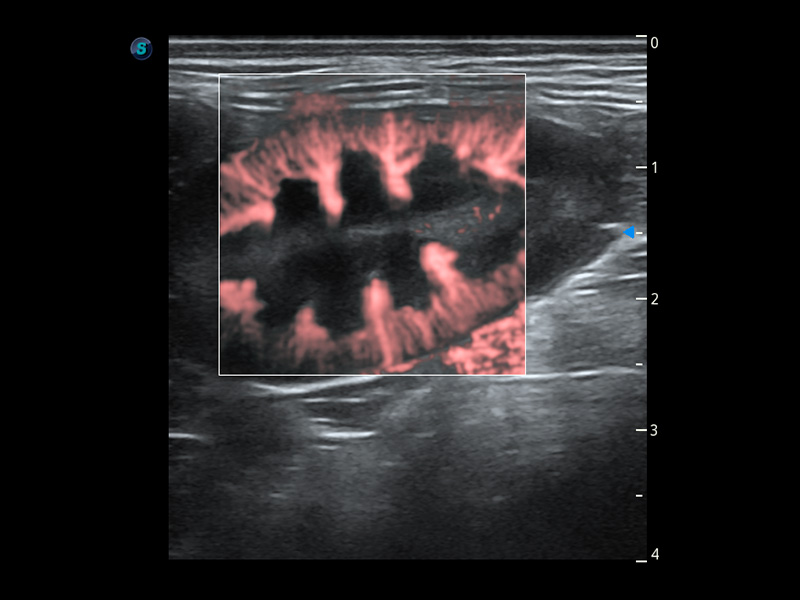

ProPet 60 作为一款高端台式动物超声设备,为动物医生的日常诊断提供了一系列贴合动物临床需求、解决临床实际问题的高级成像功能。凭借全系列高清探头,满足医生对腹部、心脏、生殖、浅表、肌骨等成像的所有需求,切实帮助您提升检查效率,提高诊断信心。

动物是人类最亲密的朋友和最值得信赖的伙伴。新葡的京集团8814检测站也一直致力于探索动物专用的超声影像解决方案。 全新推出的ProPet系列,是新葡的京集团8814检测站在动物超声影像智能化、专业化、精准化的一次跨越式革新。动物不能用言语来表述自己的不适,通过超声影像,ProPet系列搭建了动物医生与不同物种沟通的“桥梁”,为动物医生注入了“治愈之力”。